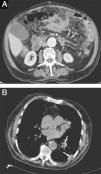

Nocardiosis abdominal seudotumoral: una presentación clínica infrecuente

Pseudotumoral abdominal nocardiosis: An uncommon clinical presentation